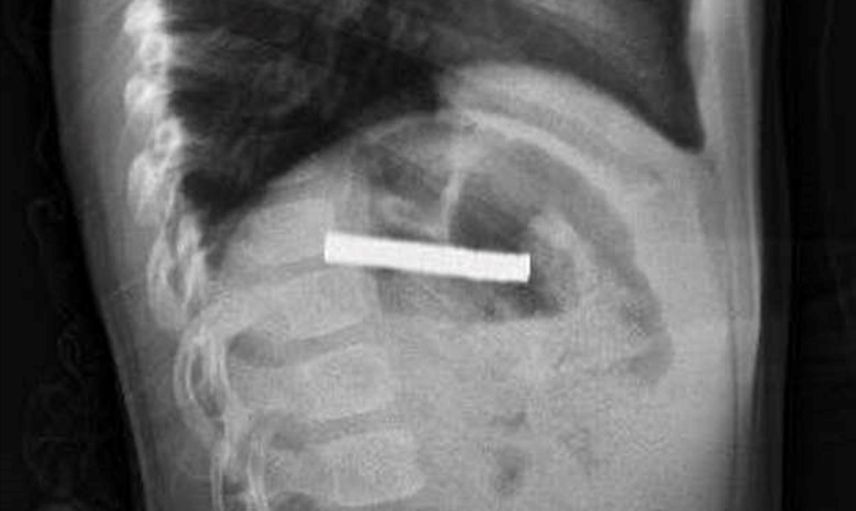

Elazığ'da 3 yaşındaki bir çocuk, oyun oynadığı sırada bulduğu 19 mıknatısı yuttuktan sonra rahatsızlanarak hastaneye kaldırıldı. Bu durum, Fırat Üniversitesi Hastanesi'nde gerçekleştirilen başarılı bir operasyonla son buldu.

Fırat Üniversitesi Çocuk Gastroenteroloji Hepatoloji ve Beslenme Bilim Dalı Başkanı Prof. Dr. Yaşar Doğan, burada yaptığı muayenelerde mıknatısların çocuğun yemek borusunu tıktığını belirledi. Doğan ve ekibi, çocuğun yemek borusundaki mıknatısları çıkarırken, işlem sırasında bazı hasarların oluştuğunu ancak iyi bir müdahale ile durumun kontrol altına alındığını ifade etti. "Mıknatıslar, hastanın midesine alındı ve oradan özel bir file ile çıkarıldı. İşlemden sonra çocuğu gözlem altında tuttuk ve sabah aile kendi isteğiyle taburcu olmak istedi," dedi.

Elazığ'da 3 yaşındaki çocuğun yuttuğu ve yemek borusunu tıkayan 19 mıknatıs, Fırat Üniversitesi Hastanesi'nde yapılan başarılı bir operasyonla çıkarıldı.